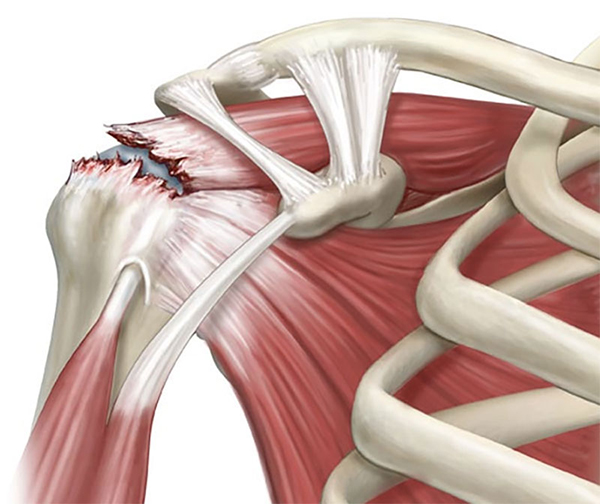

Фотографии поддельтовидной мышцы плечевого сустава